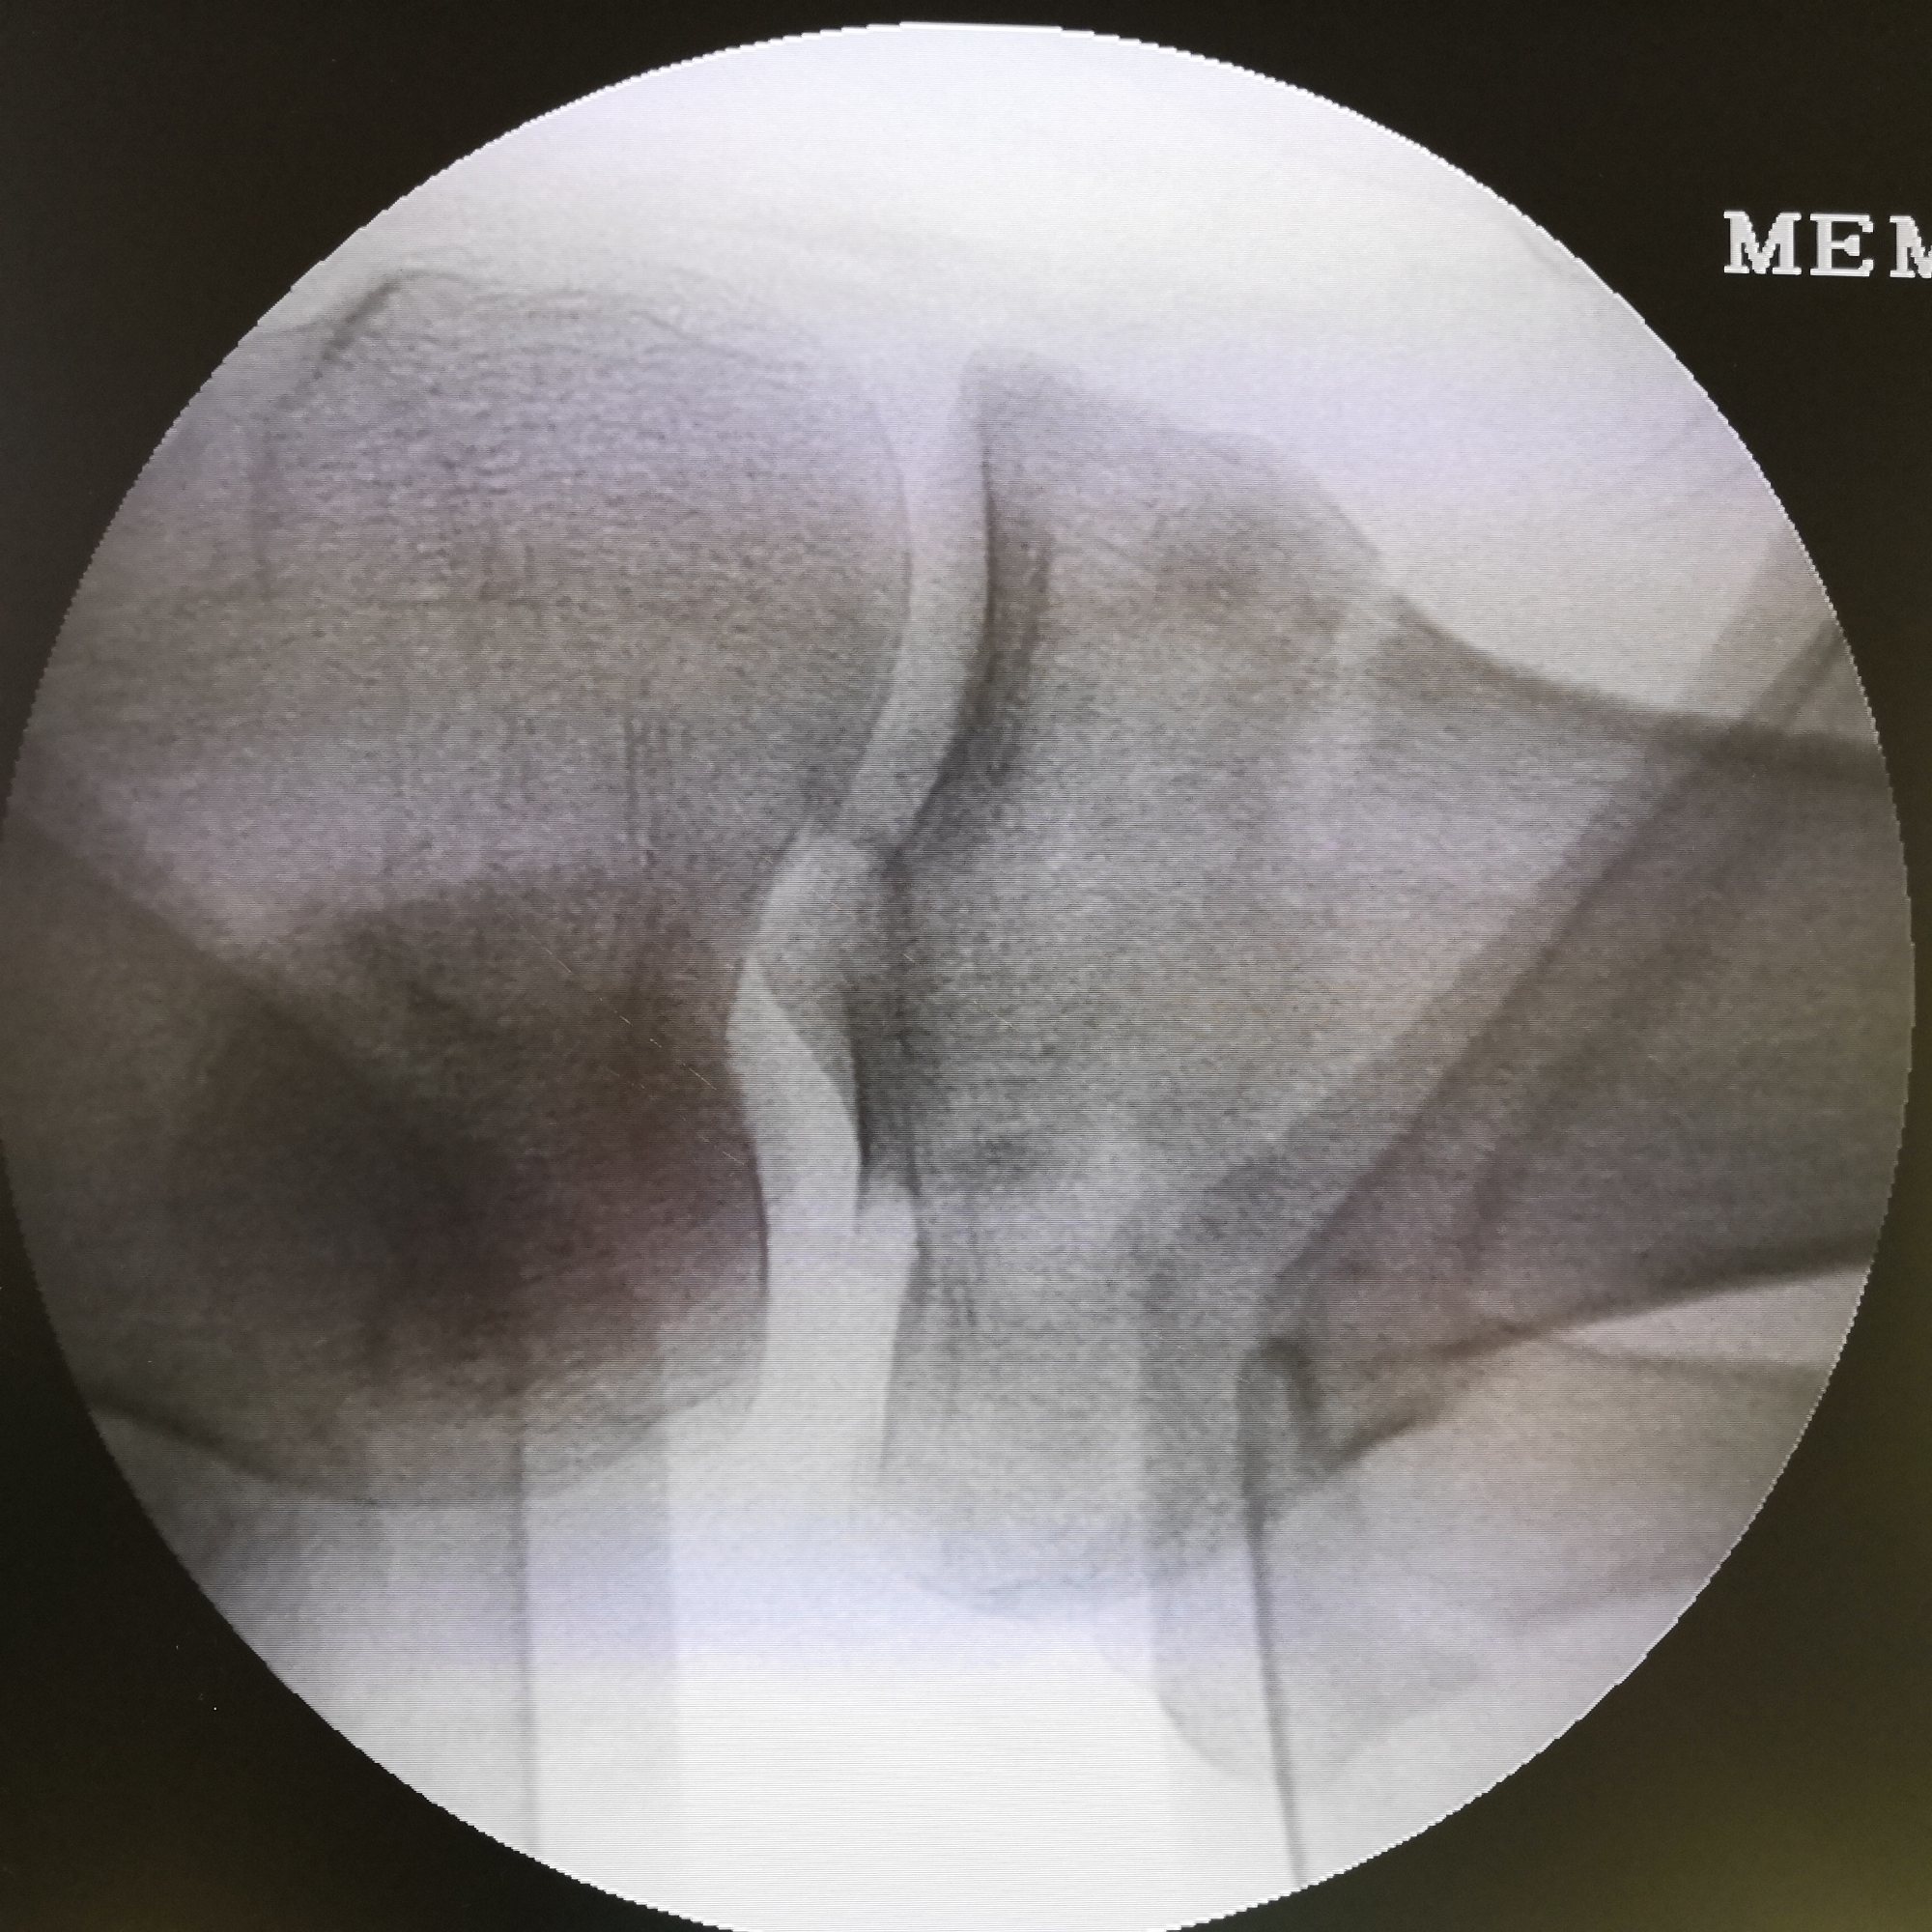

牵引 复位后X光片